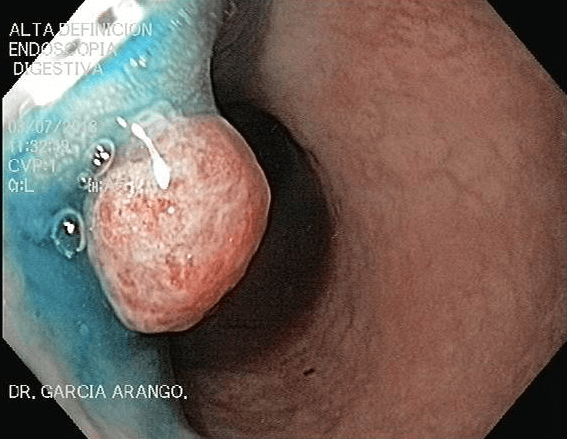

ENDOSCOPIA DIAGNÓSTICA Y TERAPÉUTICA AVANZADA CON ALTA DEFINICIÓN

⚕ Endoscopia de alta definición

⚕ Detección de cáncer de tubo digestivo

⚕ Videoendoscopia y biopsias

⚕ Videocolonoscopia